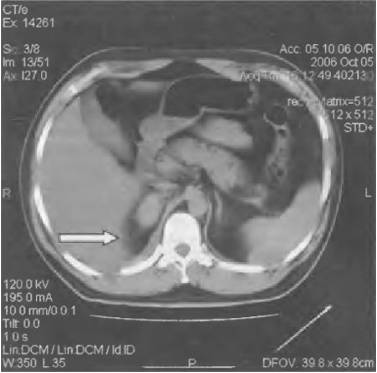

Гидронефроз

Прогрессирующее расширение собирательных полостей почек, которое приводит к их дисфункции.

Характер и локализация боли

Гидронефроз характеризуется ноющими болями в области живота, боков, поясницы и крестца.

При поражении правой почки болезненность ощущается преимущественно справа.

Дополнительные симптомы

К другим симптомам патологии относятся:

- прощупываемое уплотнение в брюшной полости;

- присутствие крови в моче;

- повышение температуры тела;

- озноб;

- головные и суставные боли.

При поражении обоих органов развивается почечная недостаточность, которая проявляется уменьшением количества выделяемой мочи, отечностью и повышением артериального давления.

Диагностика и лечение

Диагностировать заболевание можно при помощи анализа крови, УЗИ почек, экскреторной урографии, КТ и МРТ.

Консервативное лечение включает в себя:

- прием противовоспалительных средств;

- прием антибактериальных препаратов;

- использование лекарственных средств для снижения артериального давления;

- соблюдение особого режима питания.

Хирургическое лечение производится путем установки в почку стента, нефростомы.

Также проводится оперативное вмешательство для удаления суженного участка мочевыделительного тракта.